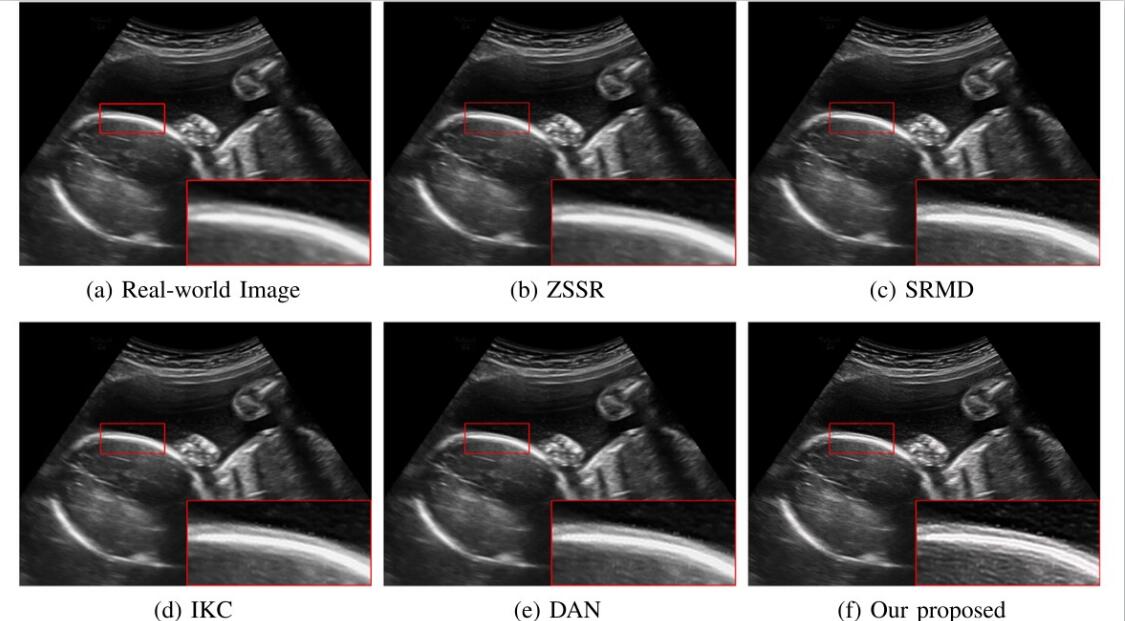

对于超声临床诊断而言,超声影像超分辨(ultrasound image super-resolution)可以提高超声成像质量,从而提高疾病诊断的准确性。但由于传感设备和传输介质的差异,实际场景中超声成像其退化模糊过程是未知且不可控的。为了解决未知退化场景超声医学影像准确超分辨的难题,团队提出了一种有效的基于退化模糊自估计且结合渐进残差学习和记忆提升机制的超声影像盲超分方法,初步实现了真实场景超声影像准确超分辨。相关研究成果发表在人工智能、计算机医学信息交叉领域一区TOP期刊《IEEE Journal of Biomedical and Health Informatics》(IF: 7.7)。必赢为论文第一完成单位,计算机学院刘恒教授、硕士生刘建勇分别为论文第一、第二作者。

(真实场景超声影像盲超分效果对比图)